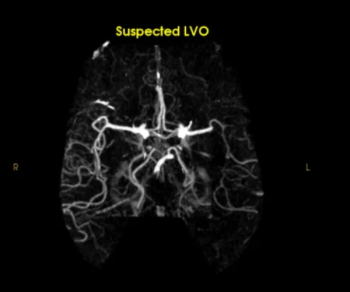

The Rapid LVO AI software detected 33 percent more cases of large vessel occlusion (LVO) on computed tomography angiography (CTA) than Viz LVO AI software, according to a new comparative study presented at the International Stroke Conference (ISC).

Offering automated conversion of computed tomography angiography (CTA) into 3D images, Viz 3D CTA reportedly facilitates real-time insights into complex neurovascular anatomy.